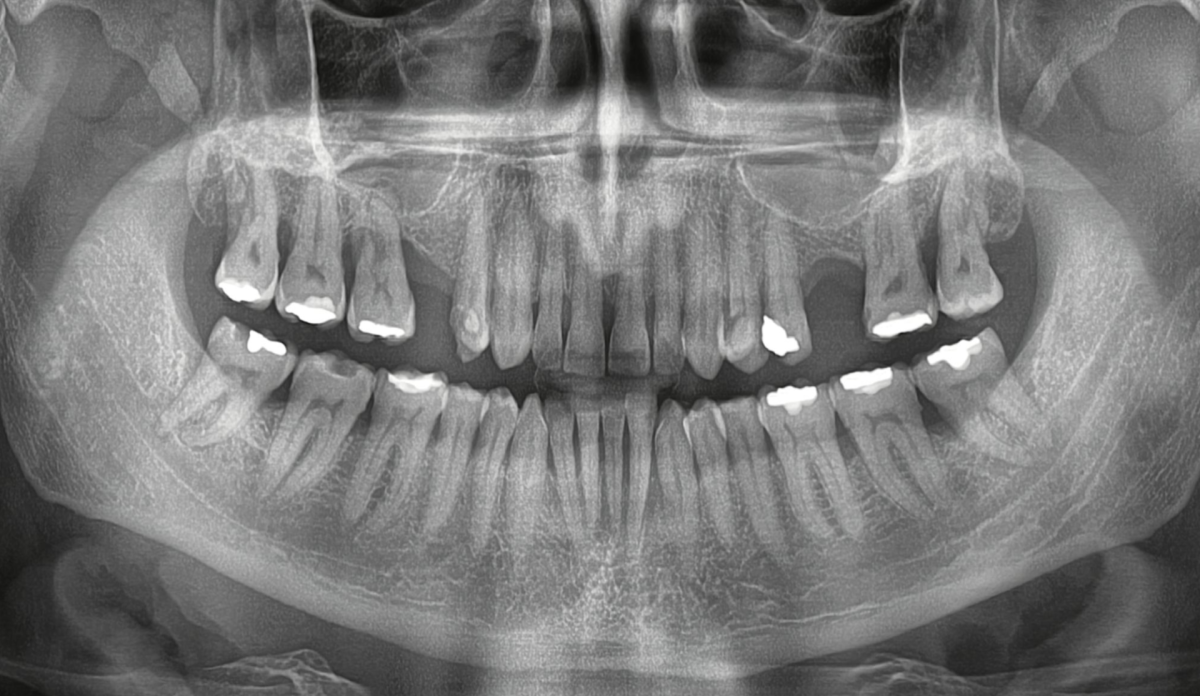

Da li ste se ikada zapitali kako stomatolog može da dobije pregled cele usne duplje samo jednim brzim snimkom? Odgovor je OPT snimak zuba, poznat i kao ortopan ili panoramski snimak zuba. Ova vrsta dentalnog rendgenskog snimanja omogućava detaljan prikaz gornje i donje vilice, svih zuba, korenova i okolnih koštanih struktura na jednom snimku.

OPT snimak je jedno od najvažnijih dijagnostičkih sredstava u savremenoj stomatologiji. Koristi se za otkrivanje impaktiranih umnjaka, cista, promena u kosti, upalnih procesa, parodontoloških problema i drugih stanja koja nije moguće uvek jasno sagledati običnim pregledom. Brz je, bezbolan i neinvazivan, a daje široku sliku oralnog zdravlja pacijenta.

Ortopan snimak zuba ili ortopantomogram je panoramski 2D rendgenski snimak koji prikazuje:

- sve zube u obe vilice

- gornju i donju vilicu

- korenove zuba

- vilične zglobove

- okolne koštane strukture

- položaj impaktiranih zuba, naročito umnjaka

Za razliku od klasičnih intraoralnih snimaka koji prikazuju samo mali deo regije, ortopan daje celokupan pregled usne duplje na jednoj slici. Upravo zato se često koristi kao prvi korak u dijagnostici i planiranju terapije.